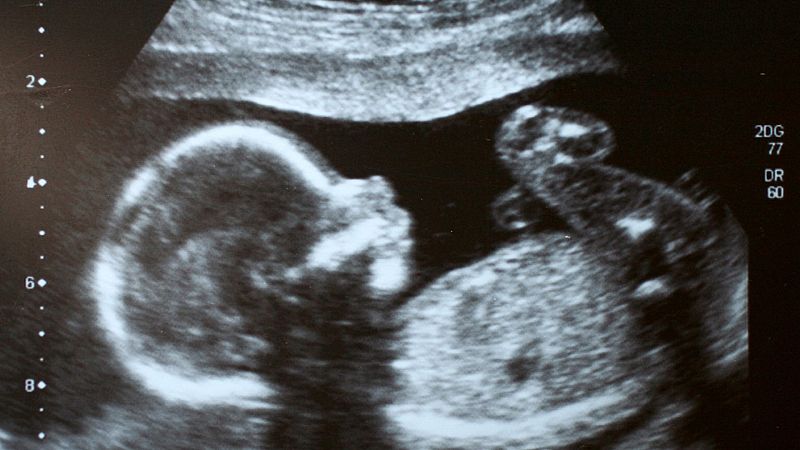

Eva se enteró de que había perdido a Sandra durante el embarazo. Recuerda cómo en una ecografía le dijeron la frase “no hay latido”. Nos cuenta que en esos momentos se sentía responsable y con remordimientos, un sentimiento común en las mujeres que sufren el duelo perinatal. "Te echas la culpa por no haber ido antes al médico, por no haber ido a urgencias, porque tenías un dolor y eso te está machacando y machacando”, explica.

Huéscar tiene constancia de que muchas familias se arrepienten de rechazarlos: “Sabemos que piden fotos de la autopsia porque es la única manera de tener un recuerdo de su bebé y poderlo conocer". Eva lamenta que, en aquellos momentos, cuando le ofrecieron una ecografía de su hija, no la quiso aceptar. “¿Cómo yo pude no coger esa ecografía de mi hija?", se pregunta. El trabajo con su psicóloga le ayudó a comprender que no rechazaba a su retoño, sino la situación que estaba viviendo.

"¿Cómo yo pude no coger esa ecografía de mi hija?"